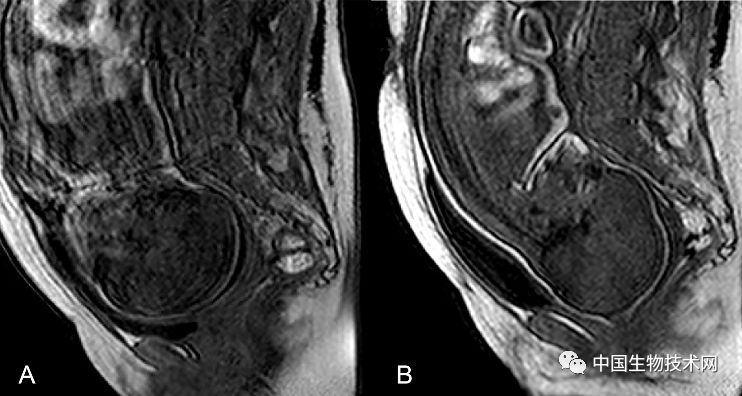

在这项新研究中,为了证明和描述胎头成型和分娩过程中大脑形状的变化,Olivier Ami博士领导的研究团队使用三维MRI捕捉了7名胎儿在分娩前和第二产程中头骨和大脑的详细图像。该分析揭示了所有7名胎儿在第二产程都有胎头成型,其中颅骨的不同部位存在不同程度地重叠。其中5名新生儿的头骨和大脑形状恢复到出生前的状态,但另外2名新生儿的头骨和大脑形状仍在变化。胎头成型程度最高的三名新生儿中有两名是通过紧急剖腹产手术分娩的,另一个是通过阴道分娩的。

图片来源:《PLOS ONE》

总的来说,该研究结果表明,胎儿在出生时承受的颅骨压力比之前所认为的要大,这可能是许多顺产新生儿出现无症状性脑出血和视网膜出血的潜在原因。

Ami补充道:“在阴道分娩的过程中,胎儿的大脑形状会根据颅骨重叠的程度发生不同程度的变形。大多数新生儿出生后颅骨成型不再明显。有些头骨顺应变形以便于分娩,而另一些头骨不容易顺应变形。”